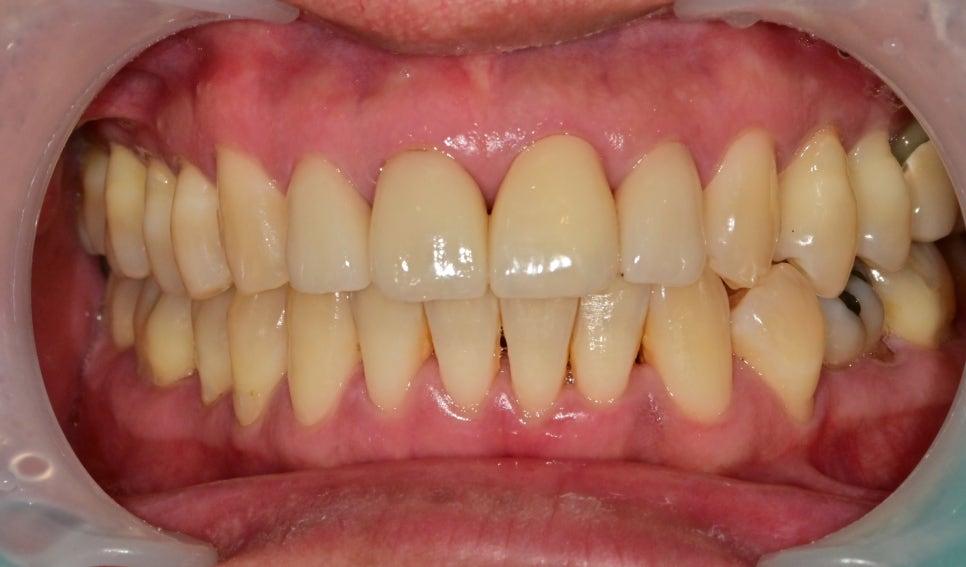

최종 크라운의 시적 후 사진입니다

최소한 크라운의 강도를 유지할 수 있는 두께로 제작했으며

대합치와의 교합 간섭이 있는 부분을 피해

오래 유지할 수 있도록 제작되었습니다.

치아가 벌어진 빈 공간을 하나의 치아로 채우다 보니

모양, 크기의 비대칭은 불가피했습니다

저의 욕심으로는 옆 치아도 같이 제작했으면 훨씬 자연스러운 형태가 나왔을텐데 하는 아쉬움이 있습니다

그래도 다행히 주변 치아의 색을 최대한 비슷하게 맞출 수 있었습니다